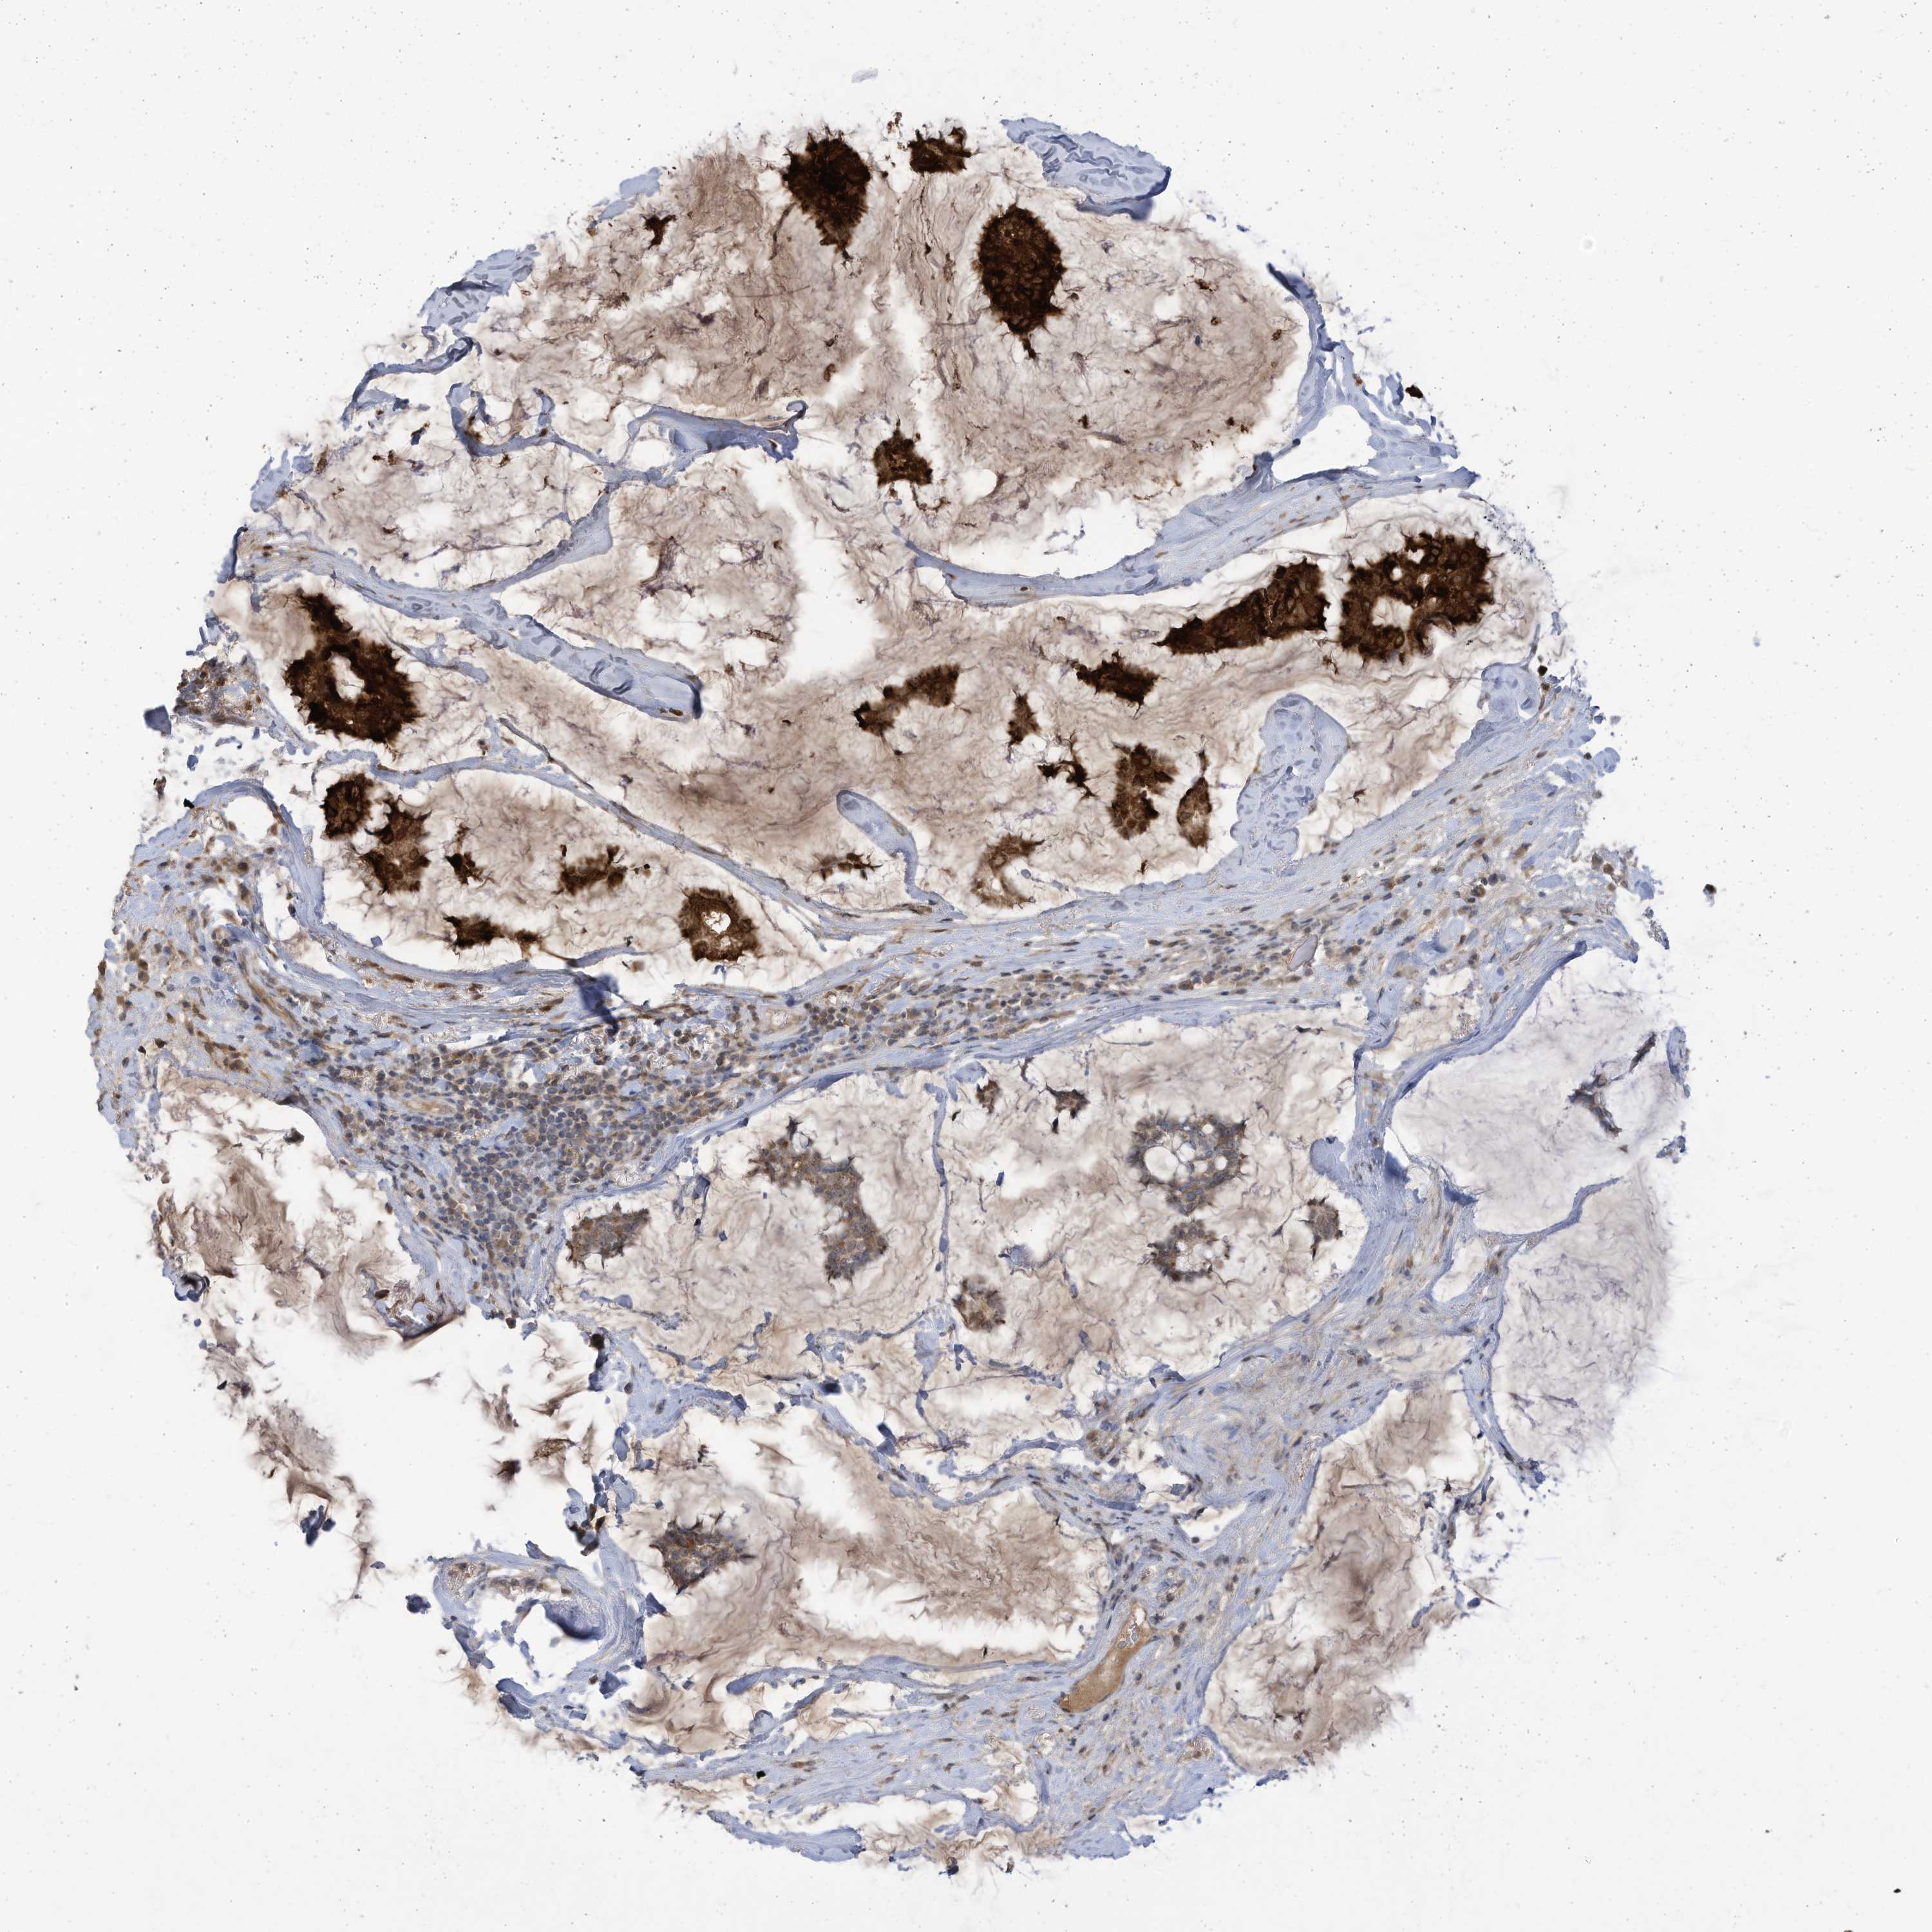

CANCER BREAST CANCER Show tissue menu

BRCA TCGA BRCA VALIDATION PROTEIN EXPRESSION